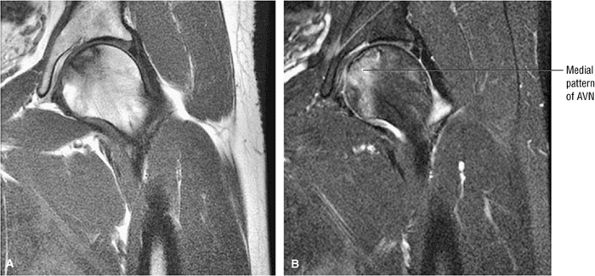

FIGURE 3.77 ● Medial osteonecrosis on coronal T1-weighted (A) and FS PD FSE images (B). Osteonecrosis involving the one third or less of the weight-bearing portion of the femur is less likely to progress to femoral head collapse.

|